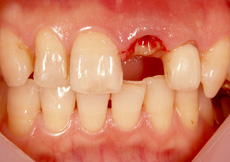

インプラント埋入のケース(前歯)

前歯が折れてしまい、ご来院されました。途中で折れてしまった歯の根を取り除き、インプラントを埋め込みました。前歯でも、ブリッジのように両隣の歯を削ることなく、見た目もキレイに修復することができます。

治療前